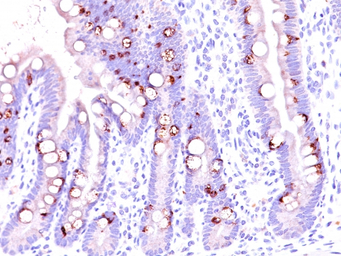

IHC-P analysis of human colon carcinoma tissue using GTX34864 MUC2 antibody [CCP58].